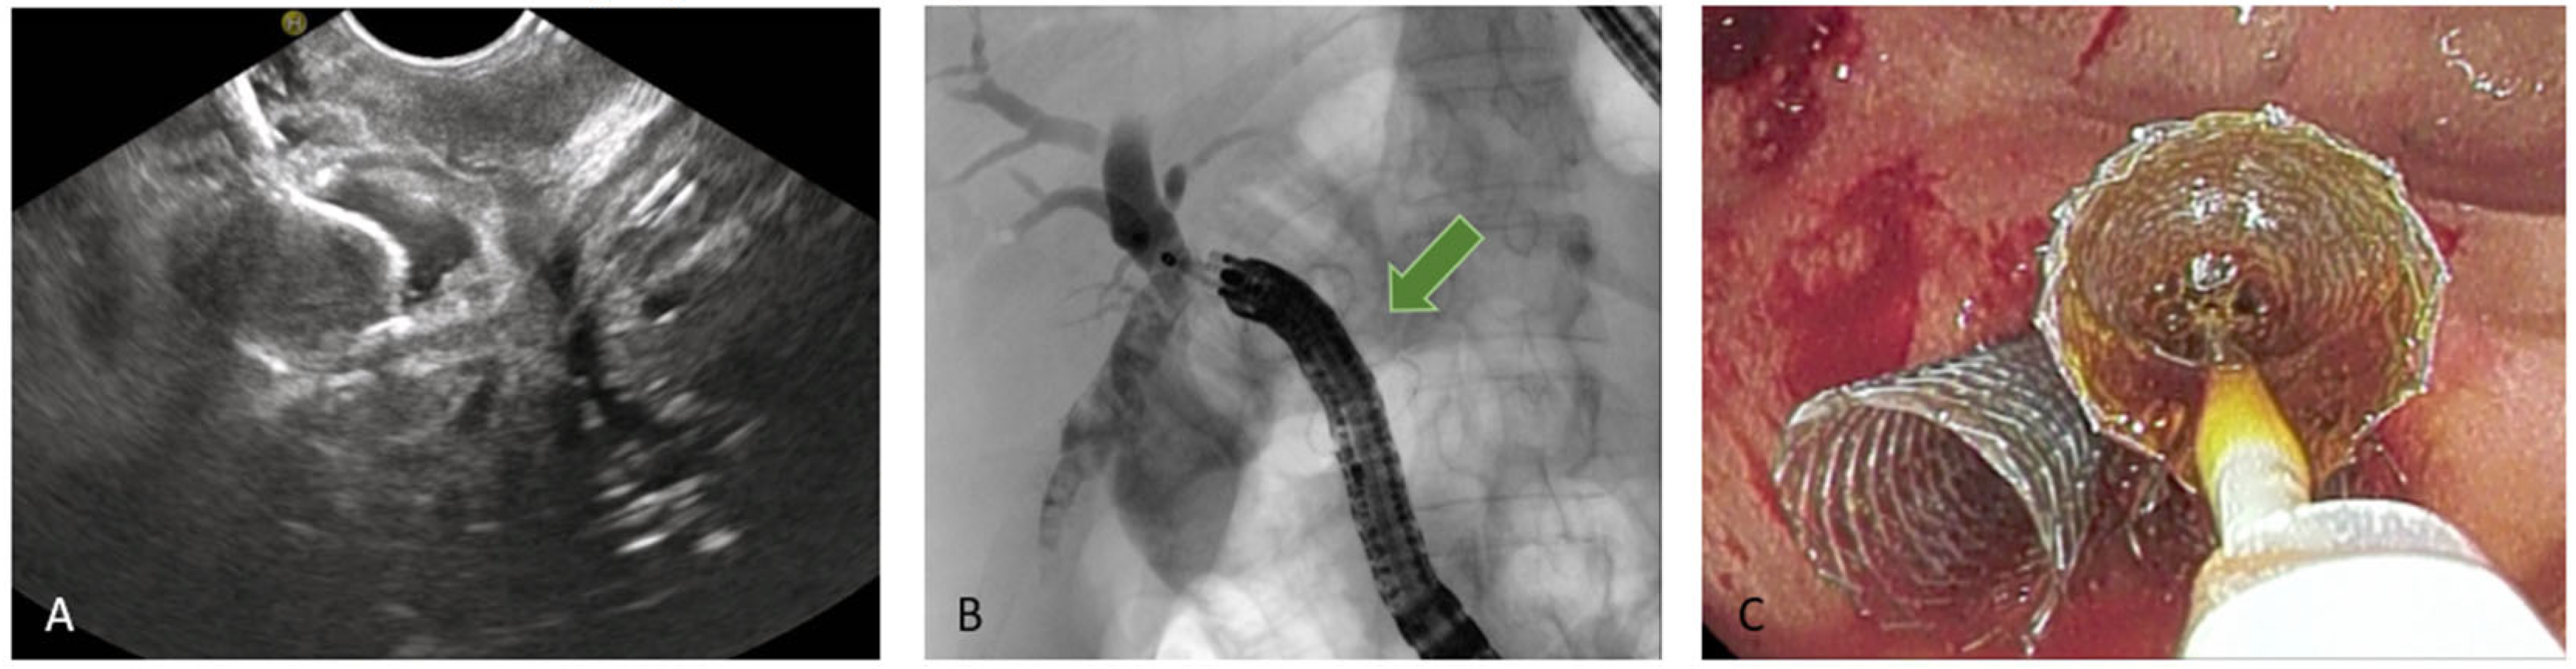

5.3.3. EUS-Guided Hepaticogastrostomy (HGS)

HGS has become a crucial therapeutic option in cases where conventional ERCP fails or is contraindicated, particularly in patients with SAA, malignant duodenal obstruction, or inaccessible ampulla. HGS creates a permanent fistula between the intrahepatic ducts (typically segment II or III) and the gastric lumen, using a hybrid SEMS specifically designed for EUS-guided HGS. It is a partially covered hybrid stent with two functional segments: the intrahepatic portion is uncovered, allowing anchorage within the liver parenchyma, while the gastric portion is fully covered and equipped with an anti-migration flange, minimizing the risk of bile leakage and stent dislodgement [38]. Before the advent of dedicated hybrid stents, and in centers where these devices are not available, plastic stents have been used (Figure 8); in this setting, a long stent is suggested to avoid dislodgement [46]. Technical aspects include careful puncture to avoid vascular structures, gentle dilation of the tract, and deployment of covered SEMS to minimize bile leak.

Figure 8. EUS-guided hepaticogastrostomy (HGS). (A) Puncture of the intrahepatic duct, EUS view; (B) puncture of the intrahepatic duct, radiologic image; (C) placement of a plastic stent to ensure biliary drainage.

Figure 9. EUS-guided duodenojejunal anastomosis (EDEE): (A) EUS-guided deployment of a LAMS into the jejunal lumen; (B) use of a pediatric colonoscope to reach the biliojejunal anastomosis through the LAMS (indicated by the green arrow); (C) fcSEMS protruding from the anastomosis.

In 2014, the first case of a trans-enteric duodeno-jejunal bypass by using a lumen-apposing metal stent (LAMS) to facilitate biliary access in Roux-en-Y hepaticojejunostomy was published [54]. To date, after more than ten years, EDEE is a consolidated and well-documented technique that represents a valid therapeutic option in patients with altered anatomy, although relegated to tertiary referral centers with experience in this type of procedure.

In this technique, a LAMS is used to create an anastomosis between the stomach or duodenum and the afferent biliary limb, thus restoring endoscopic access to the biliary anastomosis with a standard duodenoscope.

By providing a permanent and reusable access route, the entero-enteric bypass enables repeated interventions over time with standard devices. Moreover, the possibility to reach directly the anastomotic area with large-caliber scopes (e.g., pediatric colonoscope with 3.8 mm operative channel) also permits treatment of the most challenging cases with the full standard equipment (Figure 9).

The largest case series published, and subsequent expanded follow-up, report a technical success above 95% and long-term clinical efficacy above 90%. AEs included stent migration, bleeding, and leaks but were largely manageable. Compared with EA-ERCP, entero-enteric bypass is more durable and facilitates reintervention; compared with PTBD, it avoids external drains and improves quality of life [55,56].